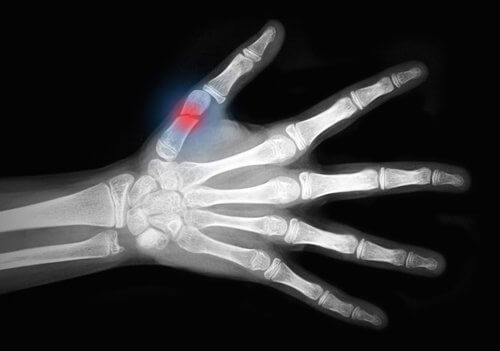

En benfraktur kan vara ett stort trauma för kroppen. Lyckligtvis är frakturläkning en av kroppens förmågor, men det kan många gånger vara en långsam process.

Därför berättar vi i den här artikeln hur du kan snabba upp din frakturläkning.